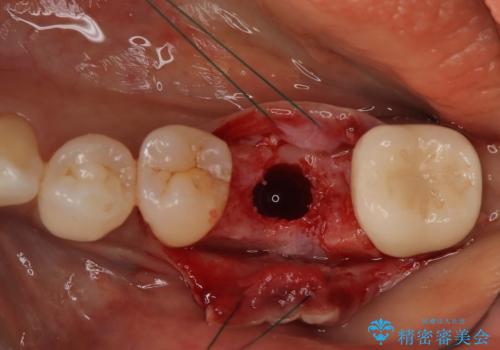

- 歯を破折により失ったため、義歯・ブリッジ・インプラント治療の3つの治療法を提案しました。

インプラント治療を希望されたため、インプラントを埋入し咬合機能を回復していきます。

骨の量は十分あったため、比較的短期間で治療は終了しました。